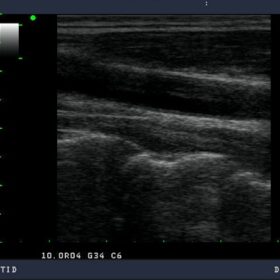

Aloka Prosound SSD-3500SX – Refurbished Ultrasound 2007

A Platform for Digital Pure Beam Imaging

The strengths of the Aloka Prosound SSD-3500SX – Diagnostic Ultrasound include clear imaging, great versatility, user-friendly design, and comprehensive data management. Enjoy the functions and performance you require in your clinical practice.

The high performance of the 3500SX stems from the state-of-the-art technologies developed for our premium performance ProSound systems. The Aloka Prosound SSD-3500SX offers great versatility over an extensive range of clinical applications with abundant specialty probes and flexible system architecture.